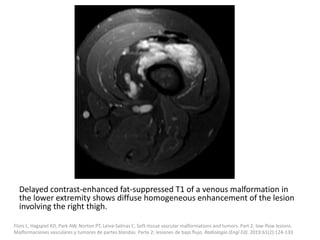

Delayed contrast-enhanced fat-suppressed T1 of a venous malformation in

the lower extremity shows diffuse homogeneous enhancement of the lesion

involving the right thigh.

Flors L, Hagspiel KD, Park AW, Norton PT, Leiva-Salinas C. Soft-tissue vascular malformations and tumors. Part 2: low-flow lesions.

Malformaciones vasculares y tumores de partes blandas. Parte 2: lesiones de bajo flujo. Radiologia (Engl Ed). 2019;61(2):124-133